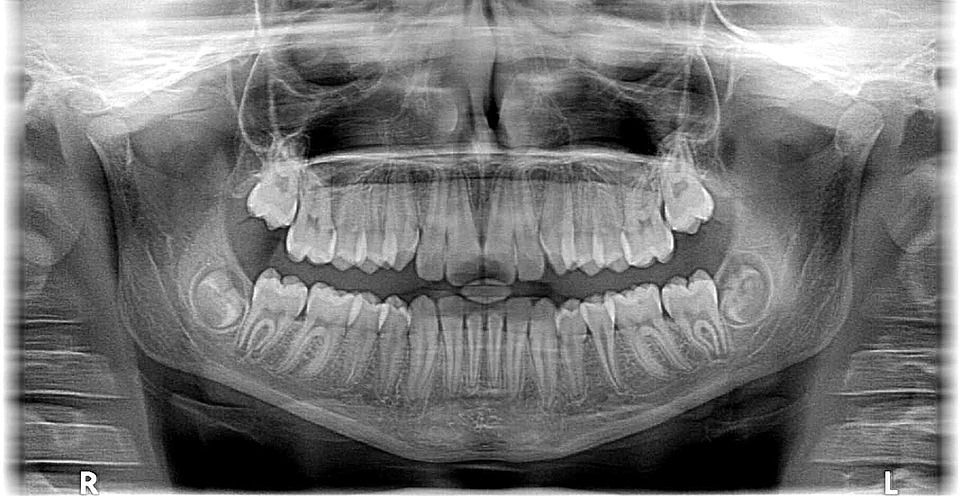

Rendgen

B-Smile nudi i zubni rendgen vrhunske kvalitete koji omogućuje brzu dijagnostiku vaših zubi. Zahvaljujući kvalitetnom prikazu lakše možemo otkriti problem i odrediti odgovarajuću terapiju.